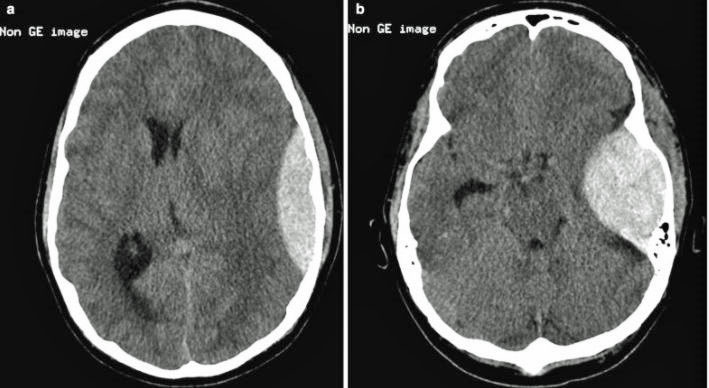

On the other hand, moderate and severe head injuries are often a neurosurgical emergency and usually have scans that are obviously abnormal, as in the MRI scan below with a large epidural hematoma (hemorrhage).

Fig 7 - Epidural Hematoma as seen in more severe traumatic brain injurySo, if the CT and MRI scans are normal in most patients with concussion and we don’t yet have any other biomarkers, like blood tests or electrical tests – we are getting closer and hopefully will have something dependable in the next few years – how do you make a diagnosis? Well, concussion is what we refer to as a clinical diagnosis – it depends on the symptoms and signs that the person is exhibiting. The table below from the CDC lists typical signs and symptoms of a concussion relevant to "sideline" or in our case "waterline" assessment.

It is also important to remember that not only are helmets important in reducing the risk of concussion / mild traumatic brain injury, but they are vital to prevent or reduce the likelihood of moderate or severe brain injury (see figures 2, 3 and 7). That is, helmets reduce the chances that you will sustain a brain injury which would require hospitalization and possibly neurosurgical intervention. If avoiding having your head opened up isn’t incentive enough then… (restrained snarky comment).4